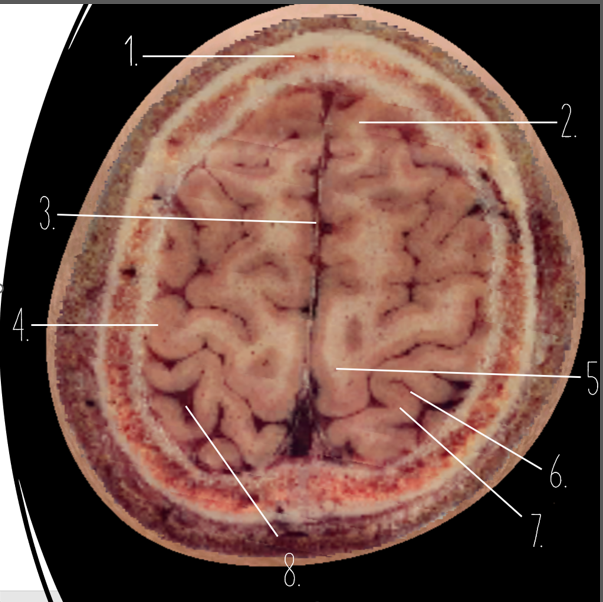

Brain Cross Sectional

1

Frontal Bone

2

Frontal Lobe

3?

Falx Cerebri

4?

Gray Matter

5?

White Matter

6?

Sulcus

7?

Gyrus

8?

Fissure